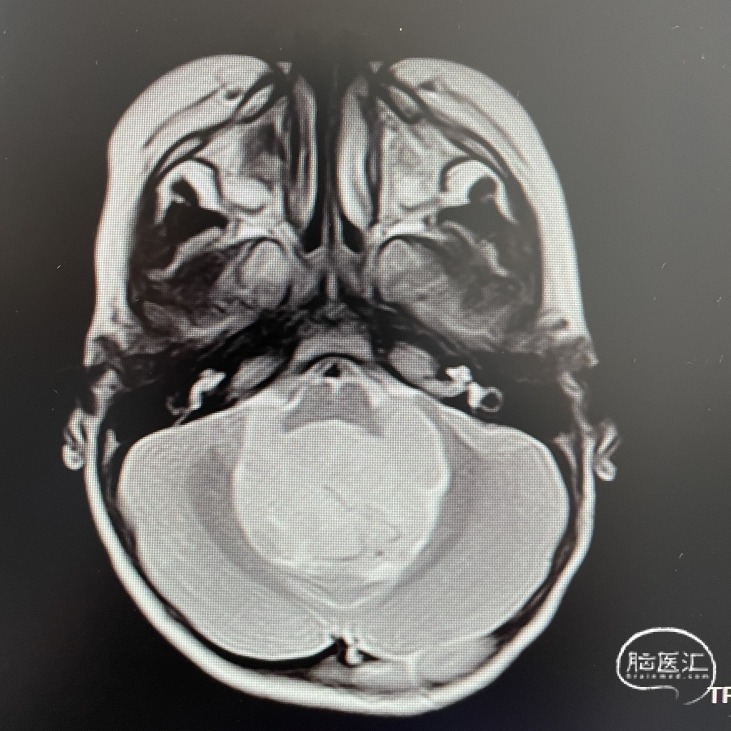

影像学资料

头部MRI检查:第四脑室扩大,其内可见一类圆形肿块,呈稍长T1稍长T2信号,边界清楚,较大截面范围约47*35*48mm。增强后呈不均匀强化;病灶向下延伸至颈段椎管内,向两侧孔延伸至桥小脑角区。幕上脑室系统扩大,周围可见片状长T1长T2信号。